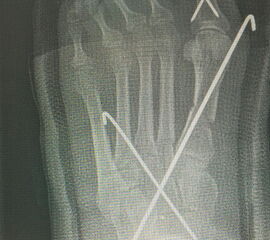

Wachstumsfugen können, wie bereits oben in der generellen Einschätzung des Verfahrens für Kinder und Jugendliche erwähnt, durch direkte Manipulation mit einer Fräse oder indirekt thermisch geschädigt werden. Eine Osteosynthese, die offene Wachstumsfugen kreuzt, ist ausschließlich mit Kirschner-Drähten oder alternativ durch externe Tapezügel möglich. Implantierte Kirschner-Drähte können ohne eine weitere Narkose im Rahmen der Sprechstunde bei verheilter Osteotomie gezogen werden. Die Anwendung von externen Tapezügeln zur Stabilisierung von minimalinvasiven Osteotomien kann bei Kindern ohne Einschränkung durchgeführt werden (siehe Abb. 4 und Abb. 12). Bei sehr jungen Kindern sollten die Tapezügel allerdings nicht zu häufig gewechselt werden, da jeder Verbands- und Tapewechsel Stress für sie bedeutet.

Abb. 12 a-b: Tapezügelfixation nach minimalinvasiver Zehenkorrektur (a) und Röntgenbild nach minimalinvasiver Zehenkorrektur mit kompletten Osteotomien und anschließender Drahtfixation (b).